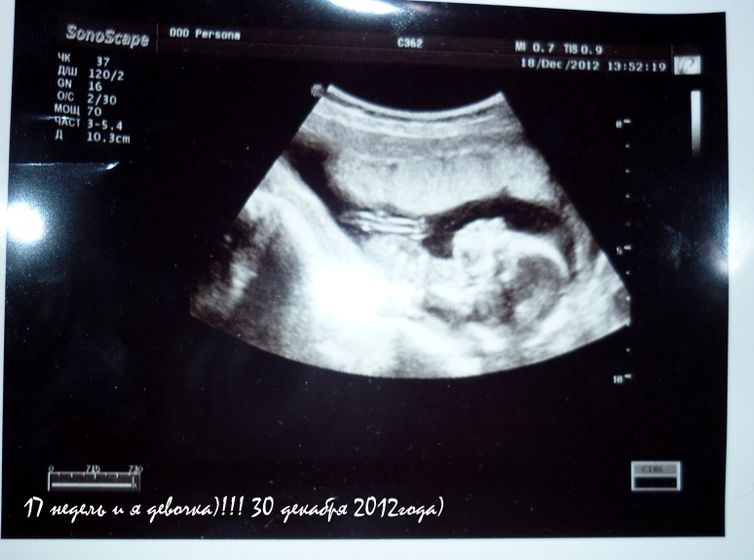

с 10й недели будет новая беременность!!! дочкой!!!